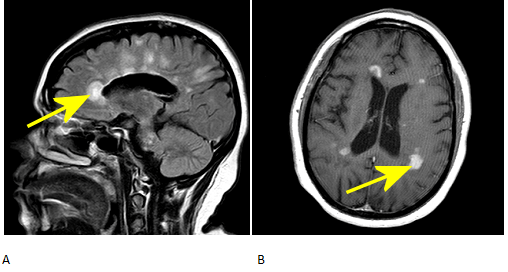

Figure 1: Yellow arrow A. Sagittal FLAIR demonstrates numerous ovoid lesions in the white matter extending towards the periventricular and pericallosal white matter. B. Several of these lesions enhance on post contrast T1 images.

Enhancement of the lesions is a sign of active demyelination. Incomplete ring of enhancement around a white matter lesion helps to distinguish a demyelinating plaque from a neoplasm. T1 hypoinstensity within the lesions (also known as “black holes”) suggests a chronic plaque.